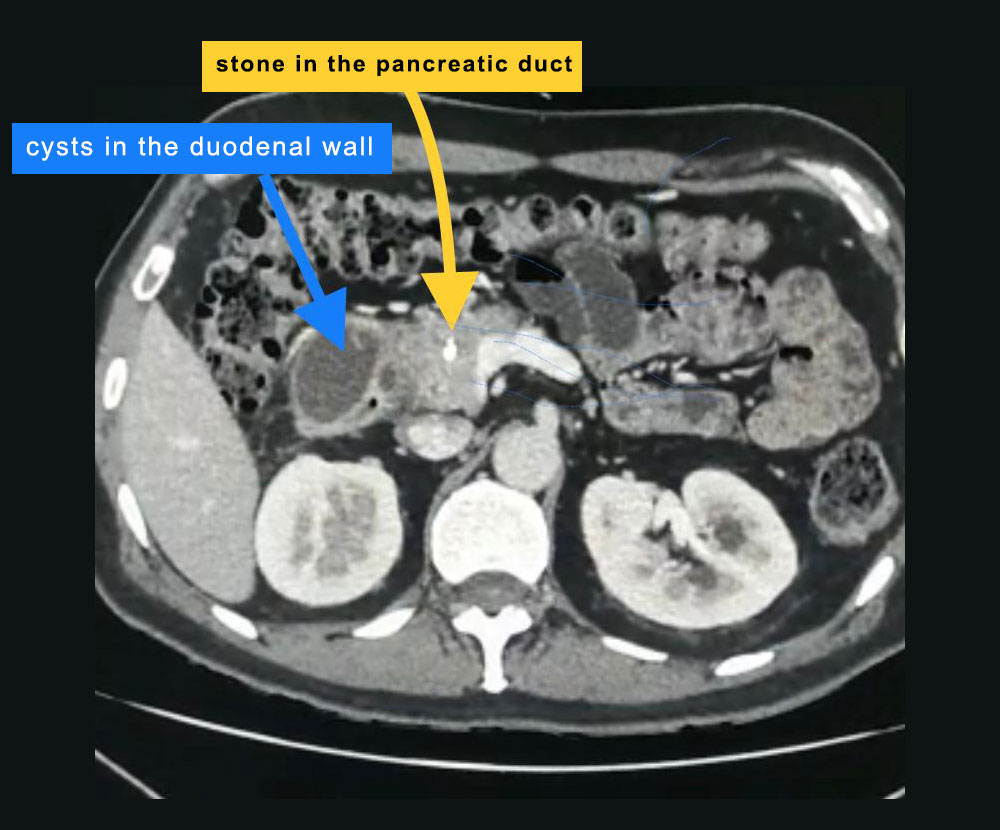

45 year old gentleman with recurrent abdominal pain on the background of alcohol intake was diagnosed to have chronic pancreatitis with pancreatic calculi and was referred to LPC for further management. On further investigation he was found to have an otherwise uncommon type of chronic pancreatitis known as groove pancreatitis and cystic duodenal dystrophy.

These patients peculiarly develop inflammation between head of pancreas and adjoining duodenum (groove). The rest of pancreas develops changes of mild chronic pancreatitis like mild duct dilatation and occasional stone in the duct. However major changes are in the groove. In the advanced form of this problem, there is severe fibrosis in the groove which may lead to the narrowing of bile duct and duodenum leading to jaundice and bowel obstruction. Similarly there can be narrowing of or clotting in the portal vein which carries blood from intestines to liver. Sometimes pancreatic cancer starts in this inflammation and is very difficult to diagnose even after extensive investigations. In rare situation there are cystic changes in the wall of the adjoining duodenum also called as cystic dystrophy. It is very uncommon form of chronic pancreatitis. We happen to have treated groove pancreatitis and cystic dystrophy both before and reported it in the international journal.

This problem is especially associated with patients having alcohol abuse and our gentleman had developed significant cystic dystrophy of duodenal wall causing abdominal pain and vomiting (due to luminal obstruction).